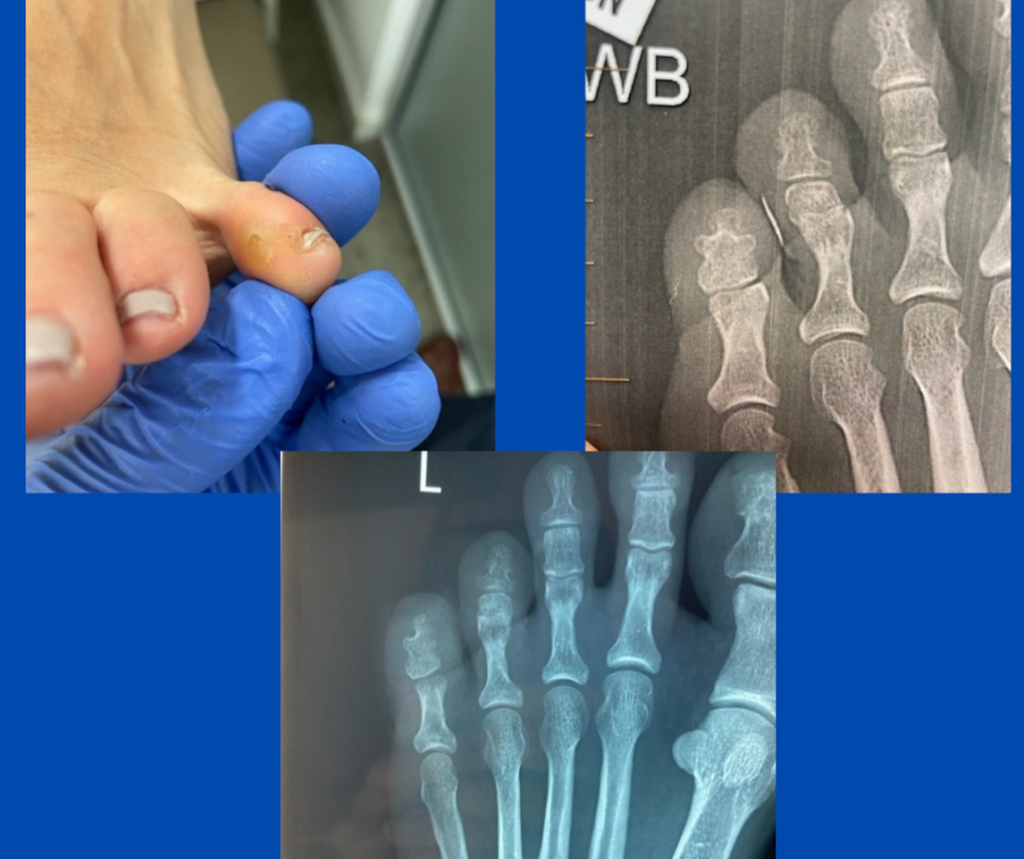

Ankylosed DIPJ and interdigital corn

Blog's main page This patient, who was referred to me for an opinion, had a markedly painful corn on the medial 5th toe that was becoming more symptomatic. On the pre-operative X-ray, it can be seen that she has a congenital ankylosed DIPJ of the 5th toe. This tends to make the toe less flexible and [...]

Blog's main page The images depict a recent case involving a patient who was referred to me for a markedly painful long-standing interdigital corn. This had recently developed an ulcer on the medial 5th toe that would not resolve. The referring podiatrist arranged an X-ray, and an obvious cause was identified. Past trauma to the PIPJ [...]